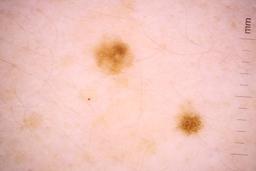

Evaluation set from the ML challenge: SIIM-ISIC Melanoma Classification.